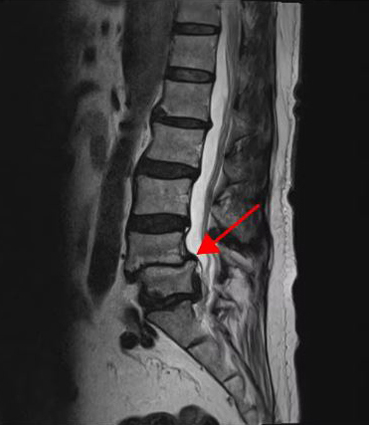

<4-5번 추간공협착증>

이 환자분의 허리 MRI를 보면 4번, 5번 오른쪽에 심한 추간공협착증과 2단계의 척추전방전위증이 있는데, 특히 척추전방전위증 때문에 추간공이 많이 좁아져 있는 상태입니다. 또 왼쪽의 다른 마디에 디스크 파열이 있으나 환자분이 왼쪽으로는 증상이 전혀 없는 것으로 보아 이 디스크 파열은 통증을 일으키지 않는 무증상의 디스크 파열입니다.

이렇듯 4번, 5번 마디의 심한 추간공협착증과 척추전방전위증으로 인해 이 환자분은 다리에 마비가 왔고, 발목에 힘이 빠져 거의 걷지 못하는 상태였습니다. 새벽에 잠에서 깨 화장실을 갈 때는 네 발로 기어갈 정도로 증상이 심했습니다. 신경주사도 많이 맞아봤지만 통증이 전혀 줄지 않아서 결국 수술을 결심하셨는데요. 대학병원을 비롯해 정형외과 및 신경외과 등 아홉 군데 병원에서 진료를 받았지만, 어려운 수술이라고 말하면서 척추유합술, 감압술 등 병원마다 제시하는 수술방법이 다 달라 큰 혼란을 겪으셨습니다. 게다가 수술 후 후유증이나 잔존 증상에 대한 물음에 ‘있을 수도 있고 없을 수도 있다’라는 의사의 말에 수술을 고민하던 중 마지막이라는 생각으로 저희 모커리에 내원하셨습니다.